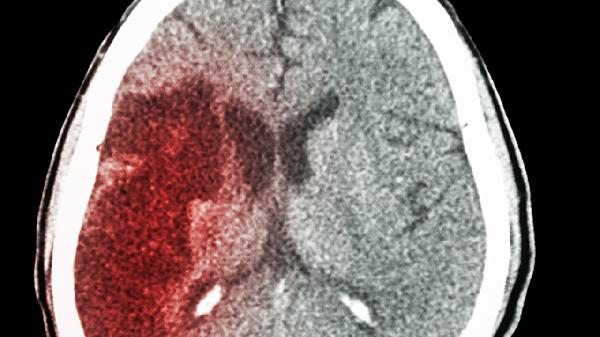

中风偏瘫的治疗方式主要包括康复锻炼、药物干预、物理疗法、中医针灸以及手术处理。这种病症多由脑梗死或脑出血引发,造成大脑组...

47岁发生脑出血导致偏瘫的患者,通常有5年以上的生存期,但具体时长会受到出血位置、并发症控制情况、康复治疗效果、基础疾病...